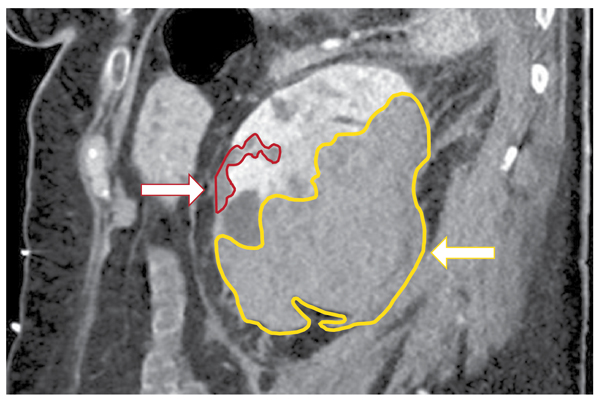

A síndrome de Wunderlich é uma síndrome hemorrágica rara caracterizada por rutura renal espontânea, não-traumática, com...